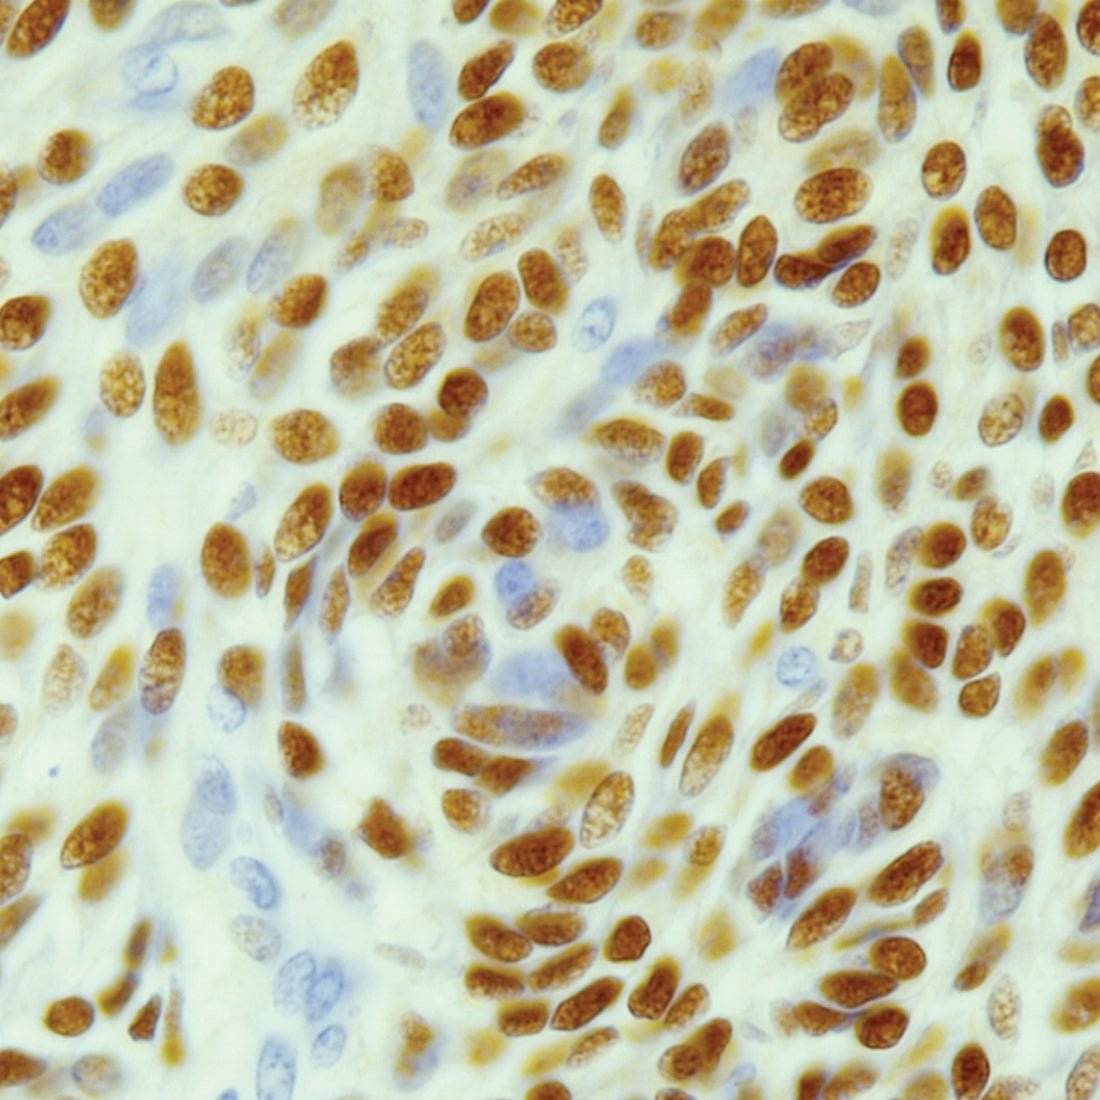

L.A.B. Solution liberates your antibody binding sites for improved immunohistochemical (IHC) staining.